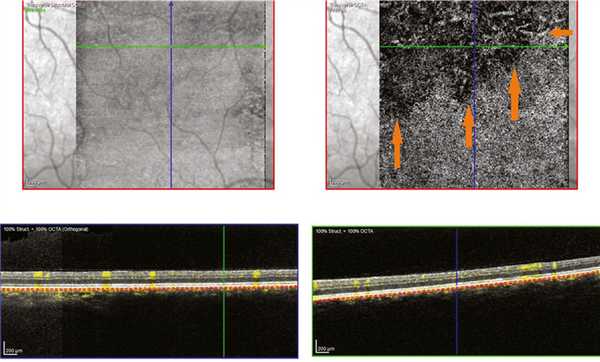

В режиме ОКТ-ангио выявлено изменение структуры хориоидеи выше фовеа — отмечено уменьшение плотности хориокапилляров и крупных сосудов хориоидеи (рис. 5). Рис. 5. Результат ОКТ-ангиографии. Срез на уровне хориокапилляров через фовеа правого (а) и левого (б) глаза. Зона обеднения сосудистого рисунка указана стрелками.

Аналогичная картина отмечена и в парафовеолярной зоне — в верхней половине выявлено обеднение хориоидального сосудистого рисунка на уровне хориокапилляров, что, с нашей точки зрения, может свидетельствовать о замедлении кровотока в расширенных сосудах хориоидеи (рис. 6). Рис. 6. Результат ОКТ-ангиографии левого глаза. Срез на уровне хориокапилляров парафовеолярно сверху. Зона обеднения сосудистого рисунка указана стрелками.